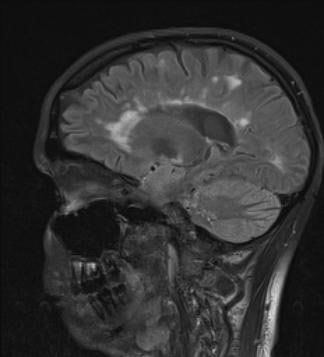

Die Diagnose der Multiplen Sklerose basiert auf folgenden Untersuchungen: In den meisten Fällen ergibt sich durch eine sorgfältige Befragung und neurologische Untersuchung des Patienten bereits ein hinreichender Verdacht auf das Vorliegen der Erkrankung. Zur Bestätigung wird dann eine Magnetresonanztomographie des Gehirns und des Rückenmarks, eine Lumbalpunktion (zwecks Untersuchung des Nervenwassers – sog. Liquor – auf entzündliche Veränderungen, den sog. oligoklonale Banden) und elektrische Untersuchungen (visuell evozierte Potenziale, VEP) durchgeführt. Dies alles sowie diverse Blutuntersuchungen dienen dem Ausschluss anderer Erkrankungen, die ähnliche Beschwerden verursachen können. Allerdings kann keine dieser Untersuchungen alleine die Diagnose MS sichern, manchmal bleibt es am Beginn bei dem Verdacht und erst im weiteren Verlauf und einer Beobachtungszeit von mehreren Monaten wird die Diagnose sicher.